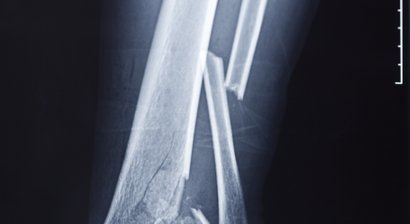

Konservative und operative Frakturbehandlung

Die Frakturbehandlung umfasst sowohl konservative als auch operative Verfahren zur Unterstützung der natürlichen Knochenheilung nach Knochenbrüchen. So können völlig unverschobene Brüche im Einzelfall z.B. mit Gips oder Orthese und Entlastung behandelt werden. In den meisten Fällen ist jedoch eine F...